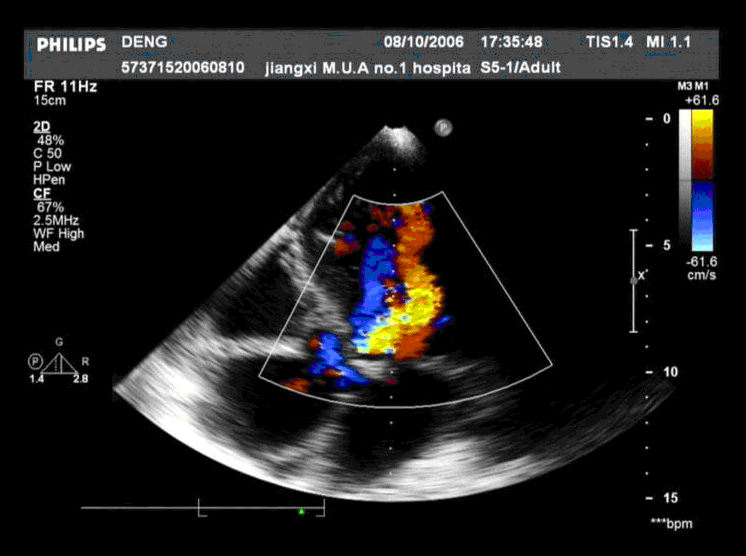

患者,男,50岁,发热半月余,全身不适,乏力,食欲缺乏。根据超声心动图,最可能的诊断是 CF20160315_19.gif CF20160315_20.gif CF20160315_21.gif CF20160315_22.gif

• B.感染性心内膜炎